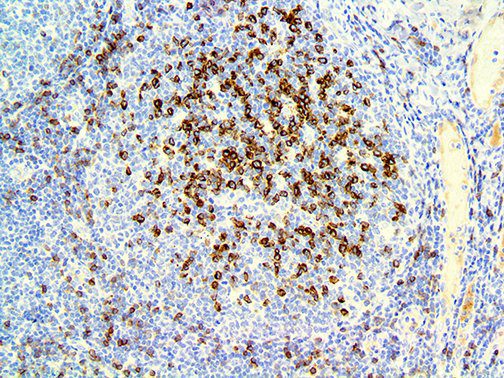

It is the ICU physician who is most likely to witness one of the deadliest manifestations of the abnormal immunological response, the cytokine storm syndrome (CSS). This response is also referred to by some as the cytokine release syndrome (CRS). CSS is characterized by continuous activation and expansion of macrophage and lymphocyte populations, which secrete large amounts of cytokines, causing the cytokine storm. This massive cytokine release is akin to hemophagocytic lymphohistiocytosis (HLH) disease, a syndrome characterized by initial unchecked and persistent activation of cytotoxic T lymphocytes and NK cells.

Clinical and laboratory manifestations of HLH include fever, enlarged liver and/or spleen, neurologic dysfunction, coagulopathy, liver dysfunction, cytopenias (i.e., low levels of erythrocytes, leukocytes, and/or platelets), hypertriglyceridemia, hyperferritinemia, hemophagocytosis, and eventually diminished NK cell activity as the immune system becomes progressively paralyzed. HLH can be familial (primary HLH) or secondary to another disease process (sHLH), such as rheumatic disease, in which it is referred to as macrophage activation syndrome (MAS, characterized by elevated ferritin).